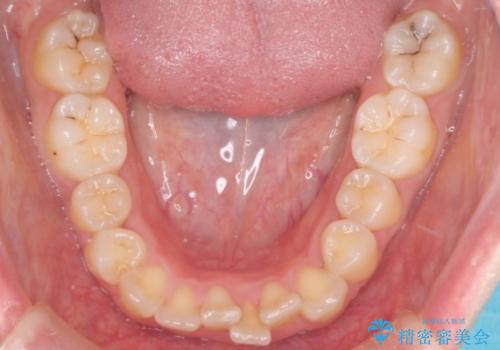

- 患者様は、結婚式までに歯並びを整えたいとのご要望で来院されました。診断の結果、上下左右の第一小臼歯を抜歯し、歯列全体を整える計画としました。審美性を重視し、目立ちにくいホワイトワイヤーを使用した矯正を提案しました。治療期間は2年を目安とし、結婚式までに前歯の整列と噛み合わせを優先的に整えるスケジュールで進めました。定期的な調整と経過観察を通じて、計画的に治療を進めました。

結婚式までに仕上げるため、通常よりも細かく調整を行い、歯の動きを効率的に管理しました。審美ワイヤーを使用したことで、治療中も目立ちにくく、写真撮影などの日常生活での見た目の負担を軽減しました。抜歯部分のスペースを閉じる際には、前歯の位置や噛み合わせのバランスに配慮し、過度な力がかからないよう進めました。患者様の大切なイベントに間に合うよう治療計画を立て、理想的な仕上がりを実現しました。